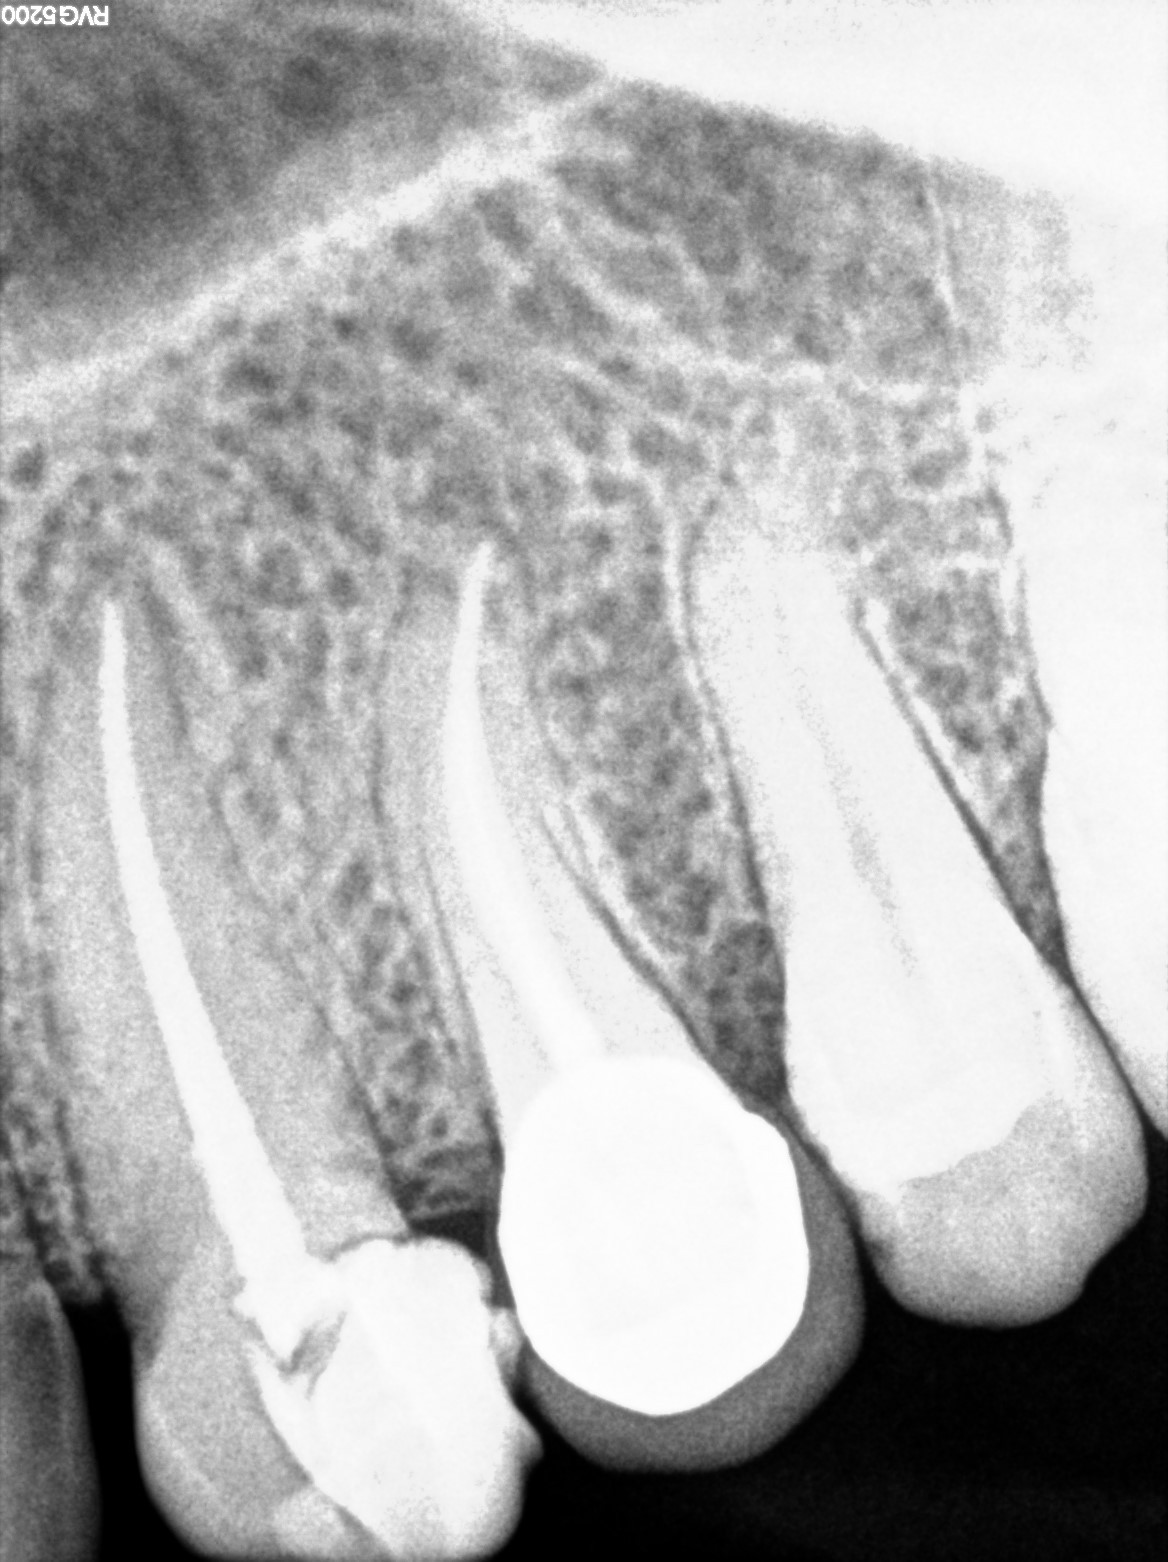

Dental Radiographs FHIR: DocumentReference · LOINC 24641-7

R58.jpg

24641-7